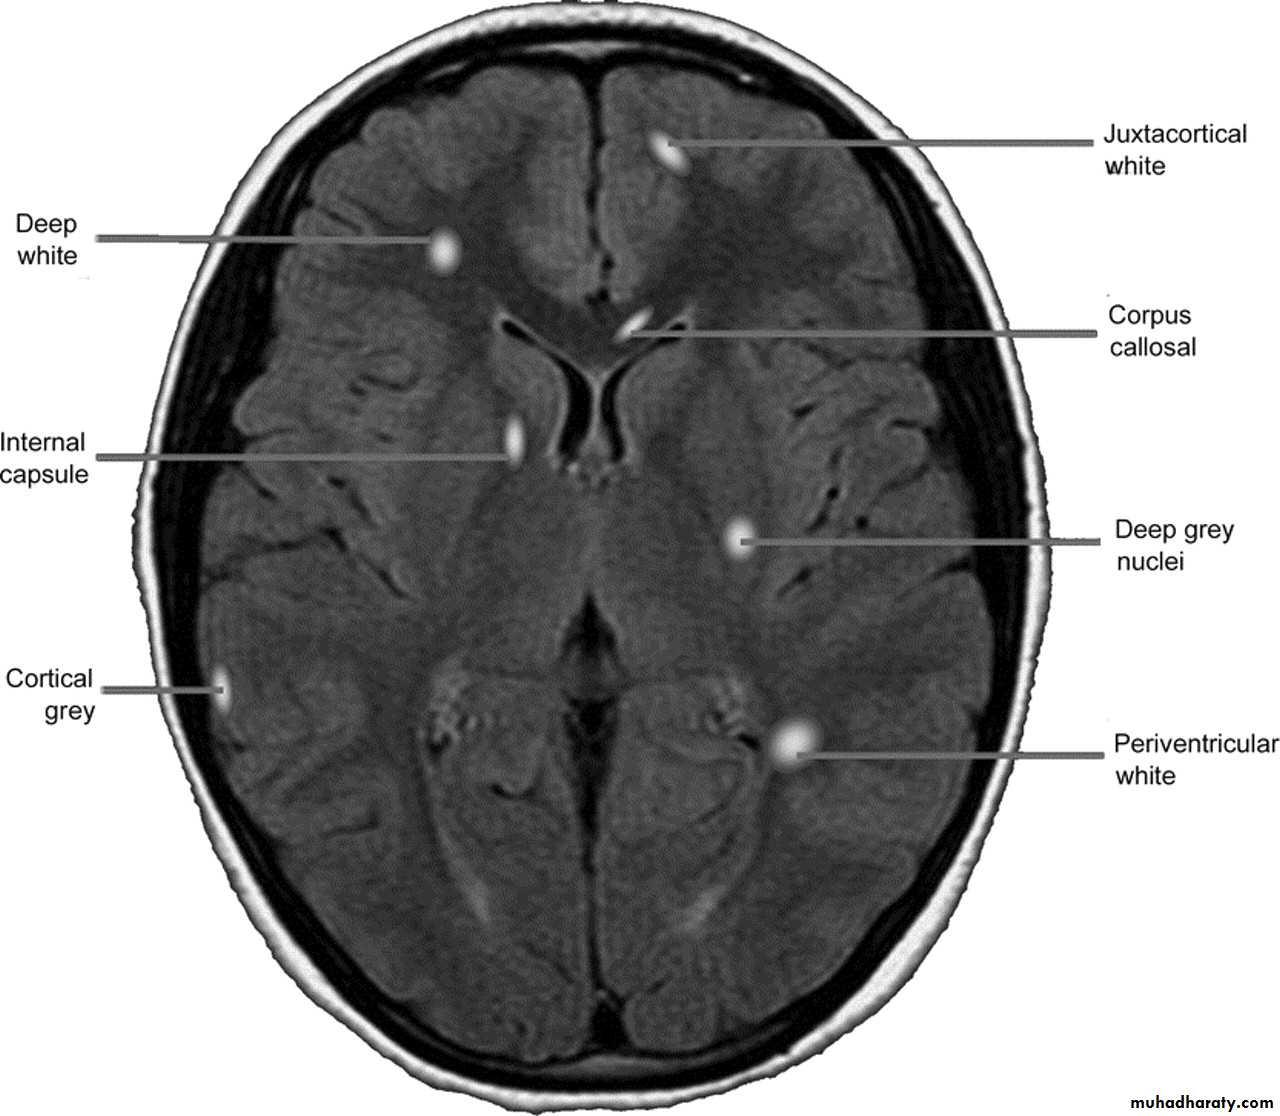

MRI :characteristic abnormalities are found in >95% of patients, although more than 90% of the lesions visualized by MRI are asymptomaticLesions are frequently oriented perpendicular to the ventricular surface,(Dawson’s fingers)

Lesions larger than 6 mm located in the corpus callosum, periventricular white matter, brainstem, cerebellum, or spinal cord are particularly helpful diagnostically